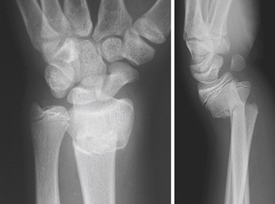

This is a displaced ulna fracture, usually proximal, with a radial head dislocation. To identify a radial head dislocation, check that the capitellum and radial head are aligned on AP and lateral X-rays.

Galeazzi fractures

Isolated radial fracture with distal ulna dislocation.

Extremely rare in children as distal ulna physeal fracture more likely.